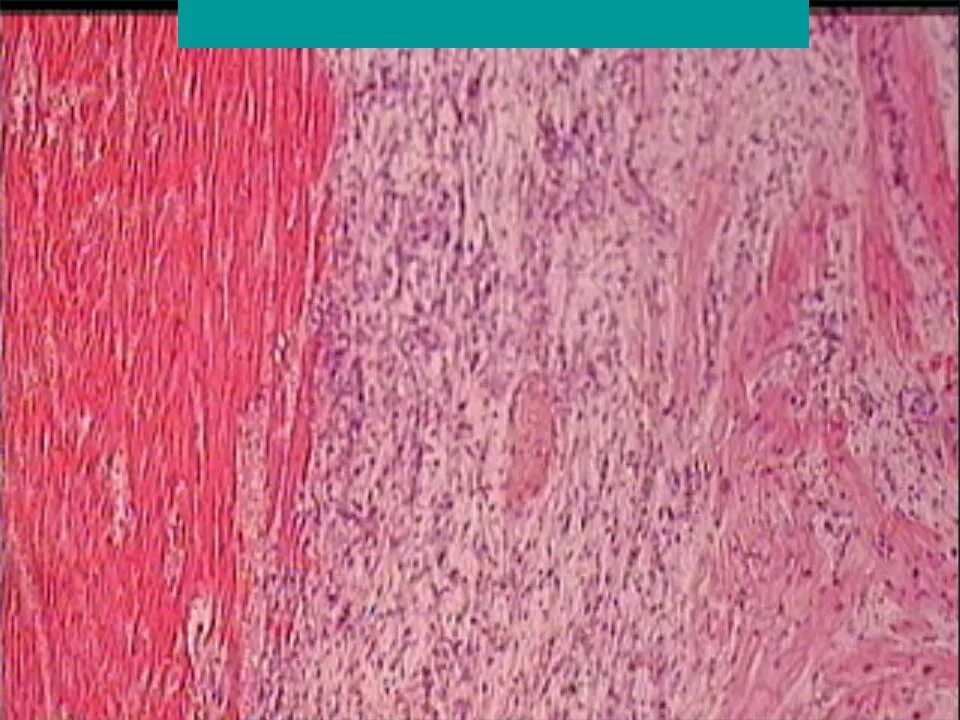

Инфаркт миокарда 2025